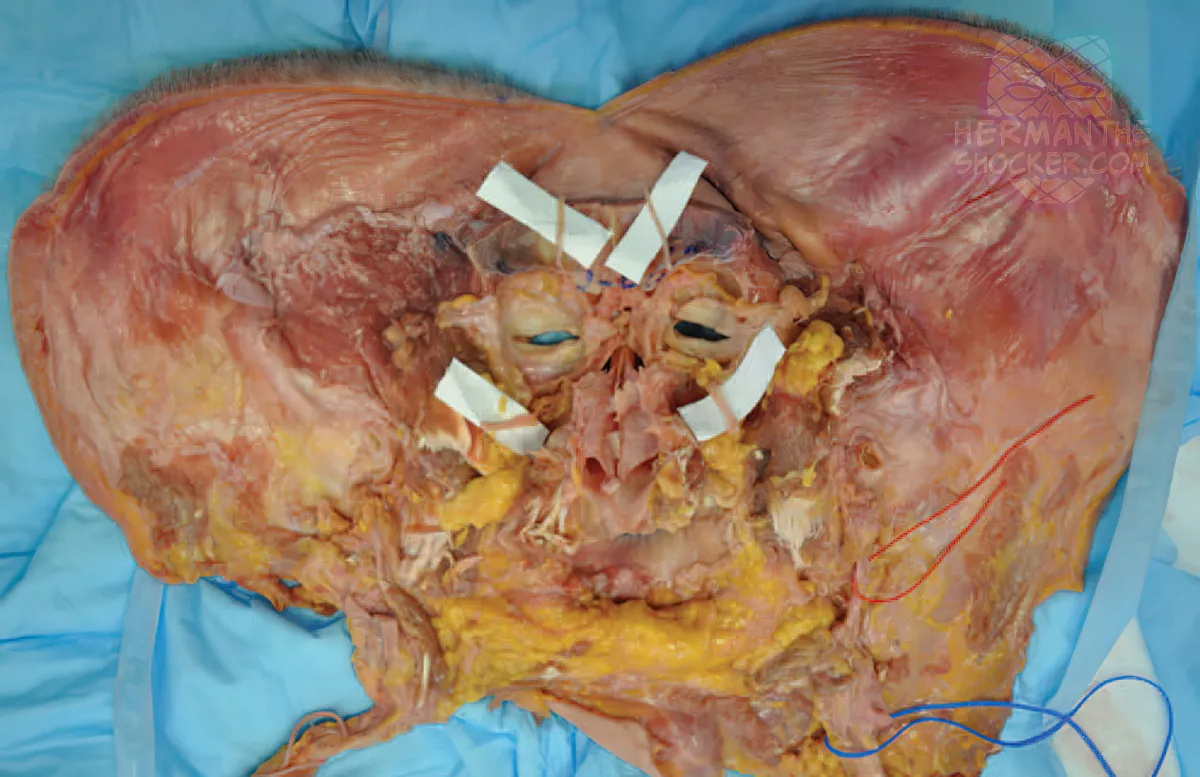

Composite facial allografts have become increasingly popular in the reconstruction of complex facial defects. Good to excellent aesthetic results can be achieved, particularly when a foundation of donor skeleton has been transferred...